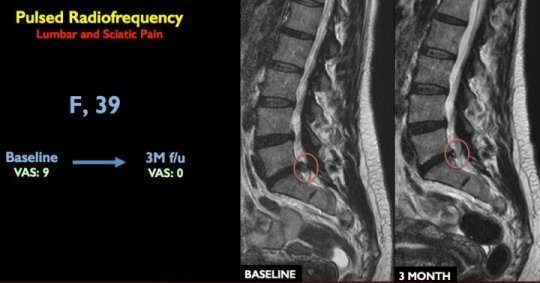

Now, a single-centre prospective study led by Dr. Alessandro Napoli has paved way for a new treatment that aims electrical pulses at irritated nerves around the spinal cord and further appears effective at relieving chronic lower back pain and sciatica.

The patients underwent a minimally invasive interventional radiology procedure in which, with the help of CT imaging, a needle is guided to the location of the bulging disc and nerve root. A probe is then inserted through the needle tip and delivers pulsed radiofrequency energy to the area over a 10-minute period. Even without touching the disc, the pulsation serves to resolve the herniation.

Of the 80 patients treated, 81 percent were pain-free one year after a single 10-minute treatment session. Six patients required a second pulsed radiofrequency session. Ninety percent of the patients were able to avoid surgical treatment.